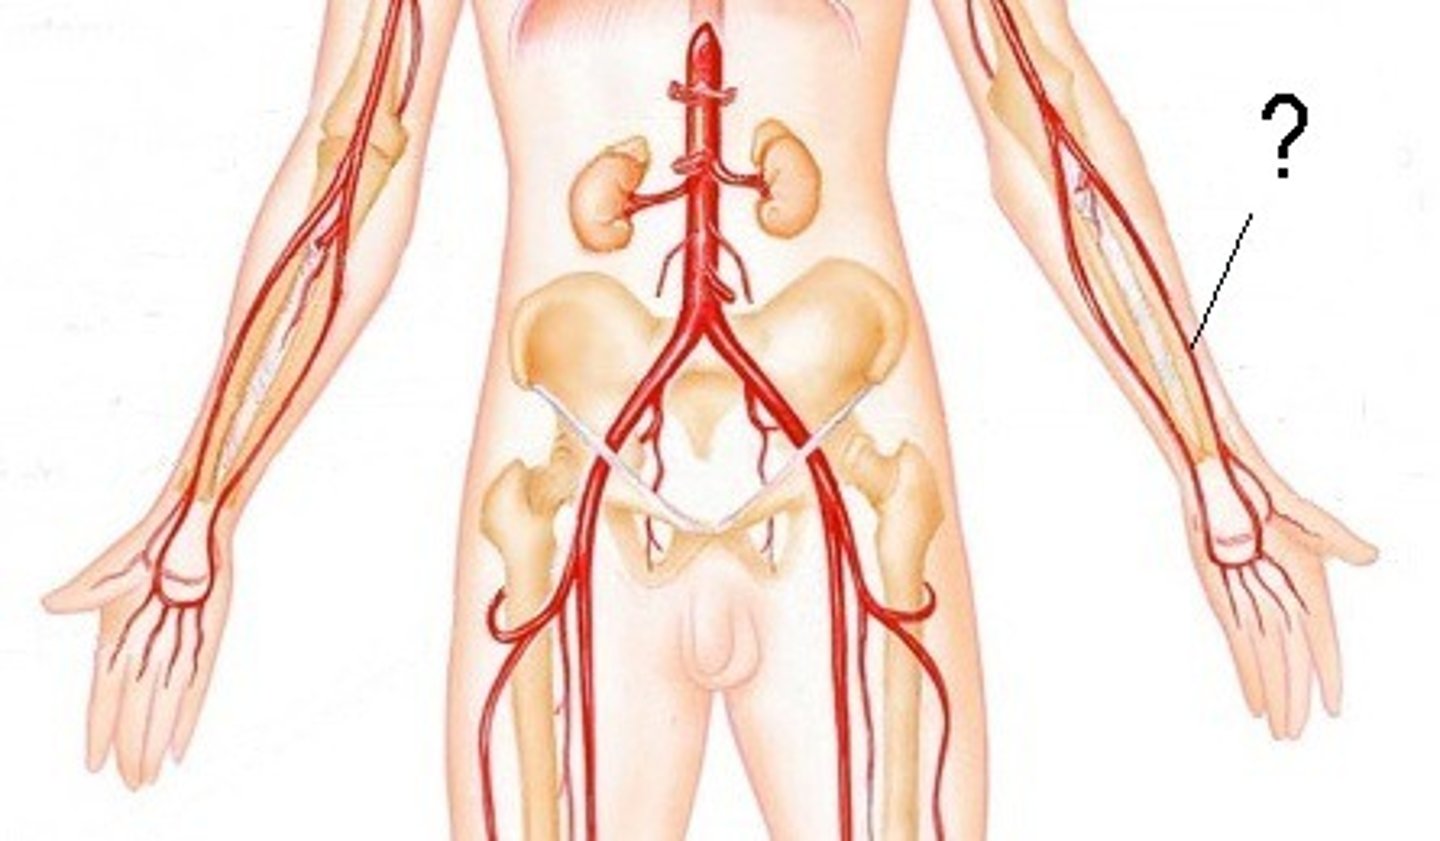

radial artery

serves the lateral forearm, wrist, thumb, and index finger

ulnar artery

serves the medial forearm and digits 2-5